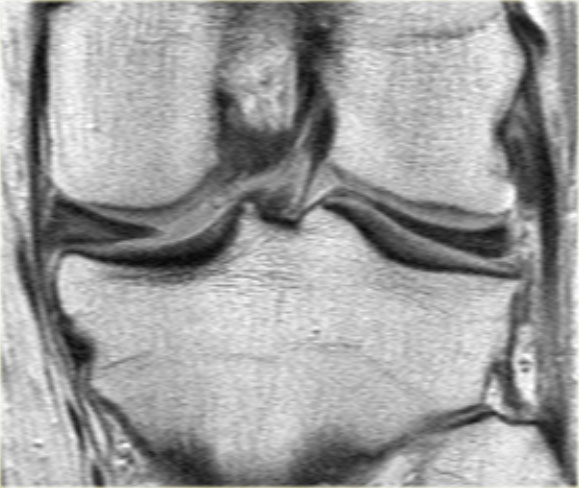

Bên trái là một trường hợp sụn chêm lật khác.

Lần này ở phía trong (medial).

Một phần sừng trước bị lật ra phía sau.

Chỉ một phần nhỏ của sừng trước được nhìn thấy ở phía trước.

Hầu hết các trường hợp sụn chêm lật xảy ra ở phía ngoài (lateral).

Dây chằng chéo trước (ACL) ngăn mảnh sụn chêm di chuyển hoàn toàn vào hố gian lồi cầu.

Trên hình ảnh mặt phẳng coronal, trước tiên sẽ thấy sừng trước to và phồng lên.

Ở phía sau sẽ thấy sừng sau rất nhỏ.

Bên trái là một trường hợp khác của sụn chêm ngoài bị lật.

- Lưu ý sừng trước rất lớn.

Phần trong là sừng sau đã bị di lệch. - Phần trong chạy vào hố gian lồi cầu.

- Phần bị di lệch được nhìn thấy rõ ràng như là ‘cấu trúc thứ ba’

trong hố gian lồi cầu. - Điểm nối với phần còn lại của sừng sau.

- Điểm nối với phần còn lại của sừng sau.

- Phần còn lại rất nhỏ của sừng sau.